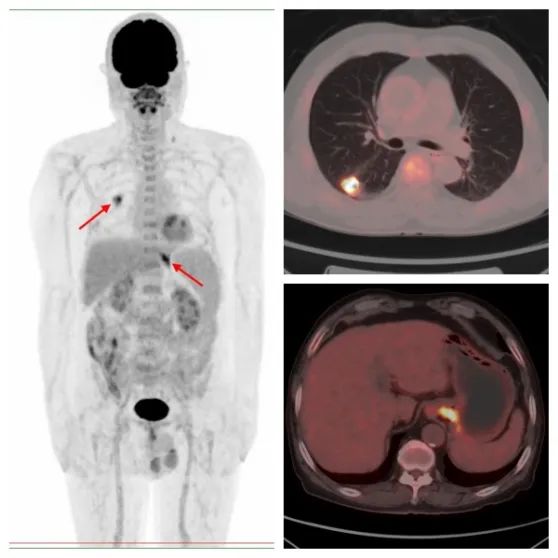

病例1,PET/CT示右肺下叶、贲门代谢异常,符合双原发癌;之后患者行CT引导下肺部病变穿刺,病理证实原发肺腺癌,行胃镜下贲门病变活检,病理证实原发贲门腺癌。